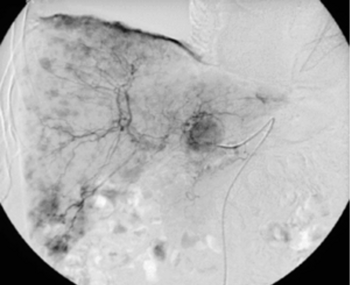

Digitale Subtraktionsangiografie: In der Leber zeigen sich multiple pathologische Anreicherungen, die Tochtergeschwülsten eines Karzinoids entsprechen.